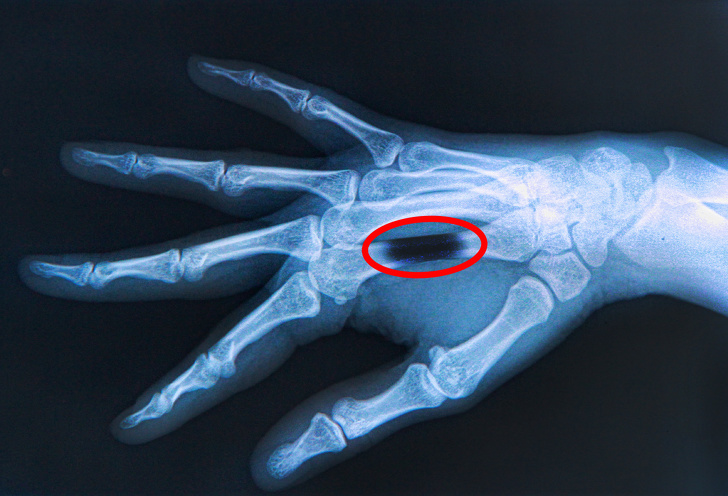

Розчинення кісток після укусу верблюда

Ніхто не підозрює, що верблюд може виявитися одним з найнебезпечніших тварин, але, всупереч переконанням, такий ризик існує. Бувають випадки, коли після його укусу в організм разом зі слиною потрапляє бактерія, що викликає остеоліз, який призводить до розчинення кісток.